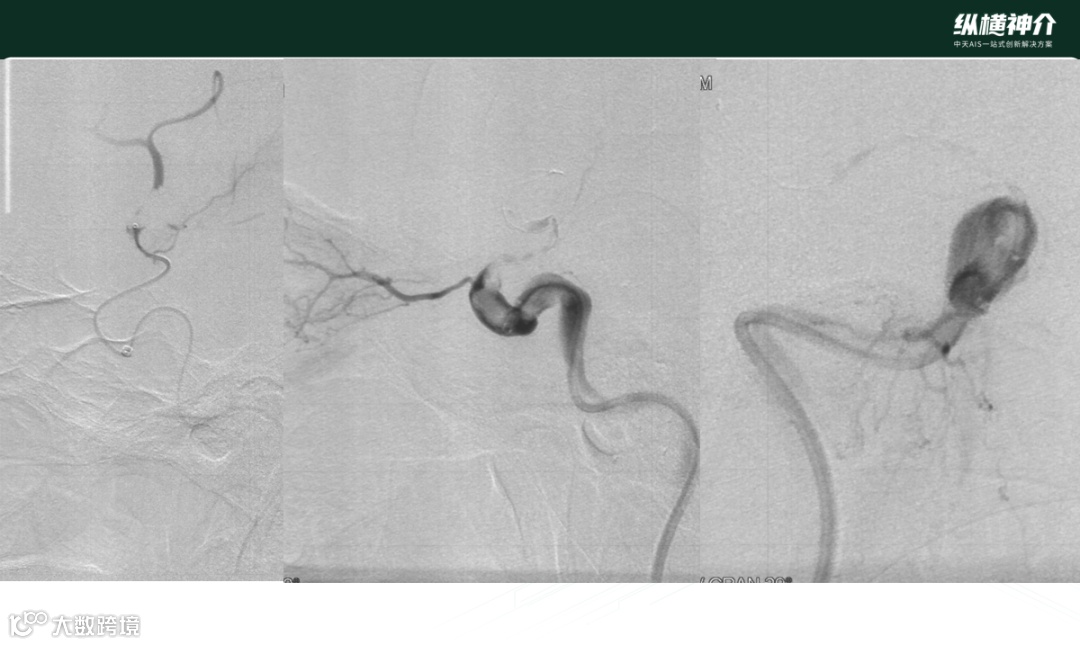

病例二

• 天弋®取栓支架 6*40mm 4*30mm

• 微导管在到达远端后,造影发现M2处也有血栓存在

• 天弋® 6*40mm取栓支架到位释放打开,显影性非常好,相比其他尺寸,对大负荷量血栓具有优势

• 天弋®取栓支架从近端到远端是缠绕血栓,而没有被近端血栓刮除掉

• 二次取栓操作,大脑中和颈内动脉血栓进一步减容

• 第三次取栓

• 天弋®取栓支架 4*30mm

• 抓捕的血栓效果来看,血栓是一个旋转的形态,用手去取下支架上的血栓比较难以取下,需要把血栓碾碎后取下。支架与血栓粘结非常紧密,临床表现优异